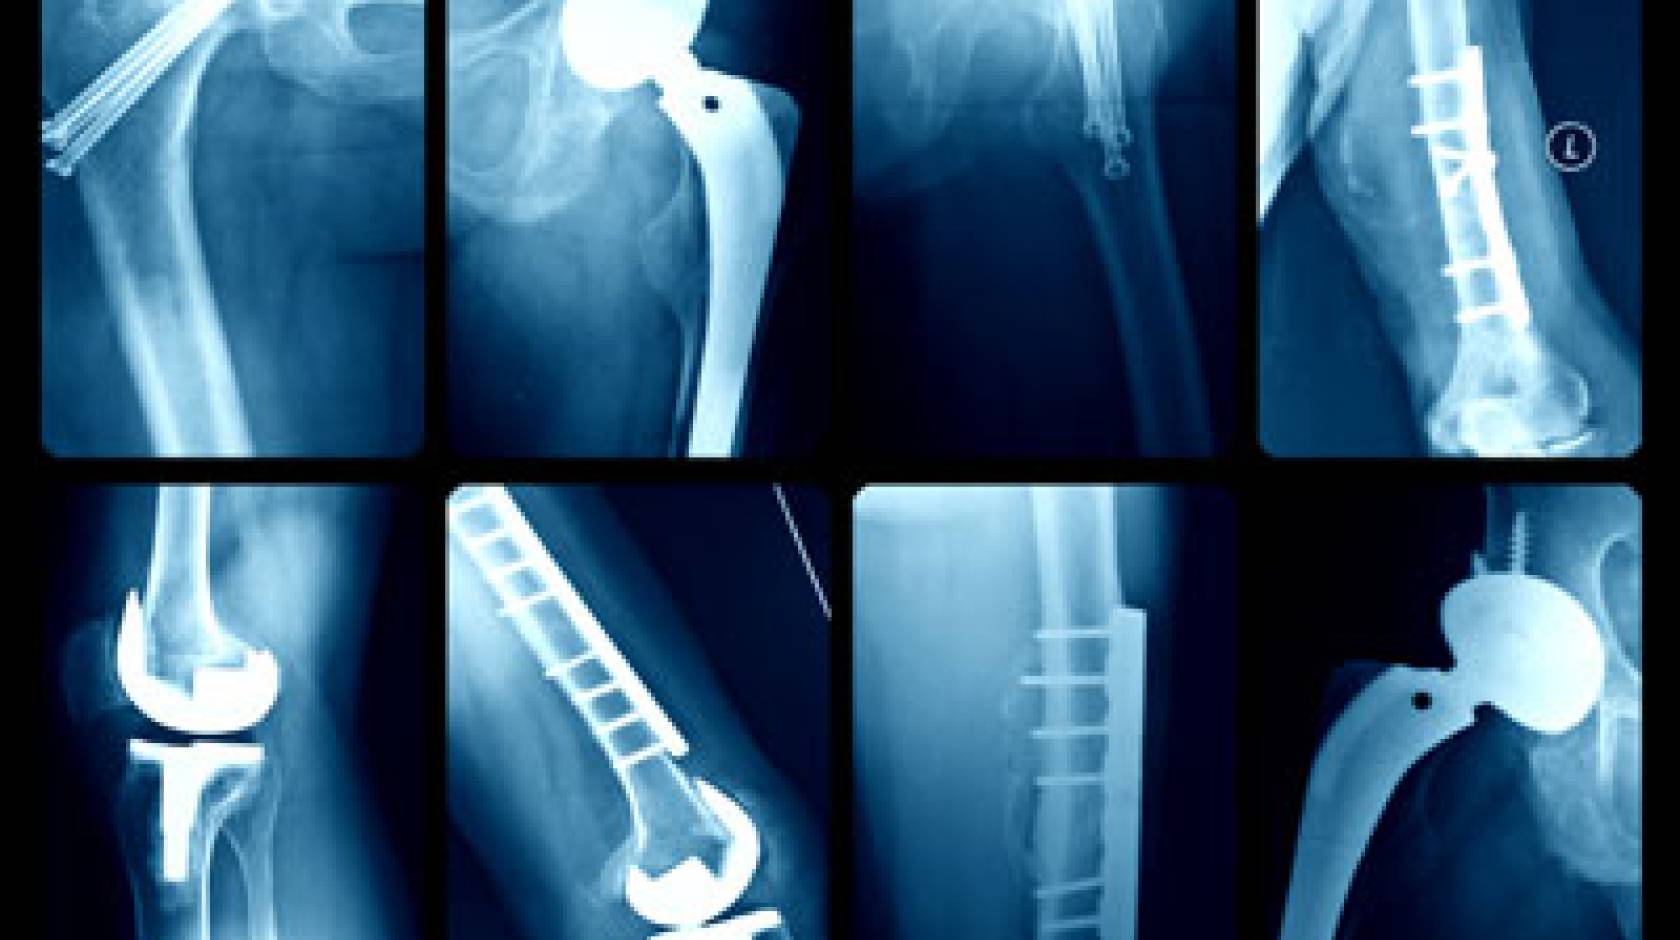

The implants are categorized by the U.S. Food and Drug Administration (FDA) as high-risk surgical devices, yet have been allowed into the marketplace without first going through clinical trials, where a product is tested to determine its safety and effectiveness. They failed at a dangerously high rate, often requiring reparative surgery at least four times as often as traditional hip replacement surgery.

U.S. hospitals perform 48 million medical procedures each year, according to the U.S. Centers for Disease Control and Prevention. Of that number, roughly 676,000 patients undergo total knee replacement surgeries and 327,000 undergo total hip replacement surgeries. While the commentary focuses on metal-on-metal hip implants, Redberg noted that there are many more devices that slip through the same FDA loopholes.